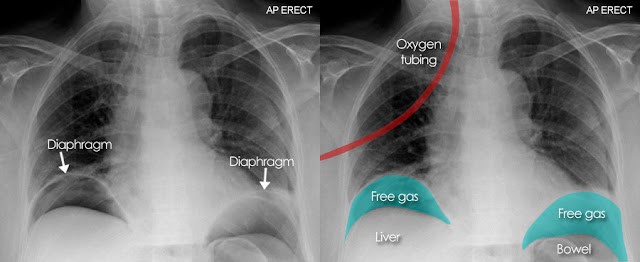

An upright abdominal radiograph is often obtained in emergency settings to evaluate other causes of acute abdominal pain, such as perforated hollow viscus or bowel obstruction, but it is not useful for diagnosing appendicitis.

Figure 2. Perforated hollow viscus on upright chest radiograph: subdiaphragmatic free air crescent